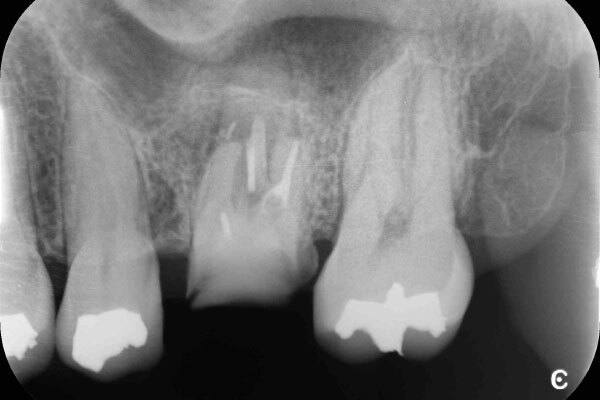

術前のデンタルX線写真と口腔内写真です。左下の一番奥の歯(#37)です。

左下の親知らずは1ヵ月ほど前に抜いたそうです。

親知らずと隣り合っていた歯の後ろ側(遠心)から虫歯が進行しています。

診査の結果、神経は正常に生きていることが分かりました。その為、いきなり神経は取らずに虫歯を取り切った上で神経を温存する治療を進めていくこととなりました。

術後デンタルX線写真

3か月後のデンタルX線写真です。

神経も正常に生きており、レントゲン写真からも異常所見は認めません。